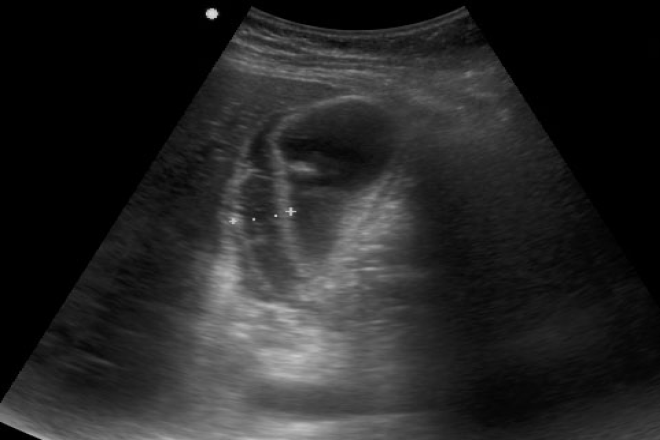

Descripción de los pacientes diagnosticados ecográficamente de esteatosis hepática en un centro de salud La esteatosis hepática consiste en la acumulación de grasa en las células del hígado y se clasifica en esteatosis alcohólica y no alcohólica. La esteatosis no alcohólica puede estar relacionada con varios factores de riesgo como